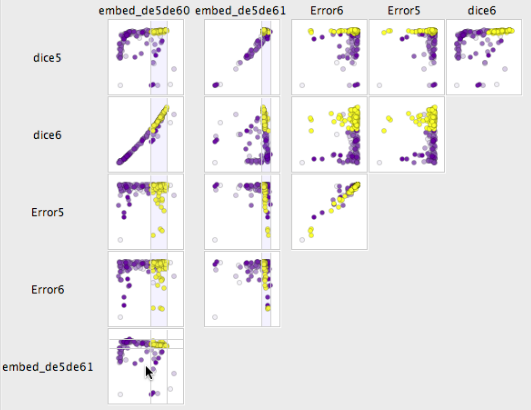

In the following, we evaluate the use of paraglide in the context of Section 2.2. During three recorded meetings of overall hours a workflow was developed, implemented, and the required interaction steps performed. The goal there was to find a robust setting for eight parameters of a segmentation algorithm that produces good results for different data sets and noise levels, assessed by ten numeric objective measures. The term good in the sense of this discussion, refers to all points on a plateau of the optimization landscape that have target values close to the global optimum. When chosen from an initial, explorative sample they are also referred to as candidates, or representatives of the good cluster. Since the optimum is an ambiguous term in the context multi-objective optimization, our method proceeds by first grouping all points that are similar to each other. This leaves the task of finding out which cluster of points is a good one. The shape of the plateau of good points viewed in the space of input parameters informed the developer about which parameters to keep and which ones to drop. It also leads to a choice of configuration for the algorithm. To enable faster computation the volumetric patient data was reduced to a single slice that contains representatives from each class.

Find good candidate points by visual inspection: For easier inspection, the full set of variables is first broken down into groups. A SPloM view of the input parameters verified that the sampling pattern indeed uniformly covers the 2D scatterplot projections. To focus on the problem, the user isolated the group of performance measures described in Section 2.2. Manually chosen configuration points improved one or two performance criteria, and allowed to verify basic data sanity in a linked data table view. A combined manual optimization of the performance measures for each of the classes, however, would require to pay attention to simultaneous changes in scatterplots. The developer considered this a very difficult to infeasible task that needed to be simplified.

Construct the good neighbourhood: For most points in parameter space, a continuous change in the input parameters leads to a continuous change in the segmentation algorithm’s behaviour and the derived performance measures. This means that for each good point, it is worthwhile to explore the neighbourhood around it to find additional good and better settings [27]. With the distinction of input and output dimensions it is possible to construct and combine different notions of neighbourhood around a point. The dialog of Figure 5 is used to combine performance measures using weights that equalize the dynamic ranges. This feature vector space is then viewed using the spectral embeddings described in Section 4.3.4.

Figure 7 shows the similarity embedding in the lower left view, where the good cluster is highlighted in yellow. Judging from the strong diagonal distribution in two plots in the matrix, the horizontal embedding dimension is dominated by dice6 and the vertical one by dice5. Since both should be maximized by good results, it is not surprising that manual inspection quickly identified the good cluster in the upper right of the embedding. The user found it convenient to make the cluster selection in the embedding, which underlines the point of Section 4.3.2. Apart from making interval selection easier, the embeddings also proved as an aid in a number of tasks: a) find good candidates, b) group adjacent good points into cluster(s), and c) check the embedding by inspecting it in a SPloM view together with the feature variables as in Figure 7.

Multi-factor assessment: To determine the relevance of each parameter for the overall performance of the segmentation algorithm, the developer viewed the distribution of the good cluster in input parameter space. This also gives a notion of sensitivity, where a large enough size of the good region indicates stability w.r.t. parameter changes [33, Sec. 1.2.3].

When projecting the cluster onto each variable individually, its shape can be either spread out or localized in one or multiple density concentrations. If the good points in the example of Figure 8 are spread out along a dimension, the corresponding parameter is unusable for steering between good and bad performance, as in this case for “don’t care” parameters alpha{1,2,7}. Observations like that inform the developer of energy terms to drop and, hence, directly influenced algorithm development. Parameters showing more localized good points or a clear transition are kept as part of the segmentation model and are set to some robust value that is further from the boundary, inside the good region.